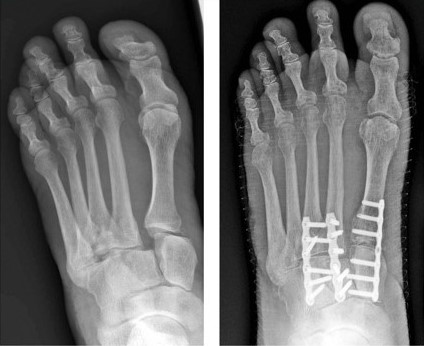

Internal fixation of Lisfranc injuries

Various methods of internal fixation can be used to fix Lisfranc injuries depending on the injury pattern. (Left) Multiple screws can be used. (Center) A combination of plates and screws may be needed when fractures are present in addition to a torn ligament. (Right) Plates that span the joints are also an excellent method of fixation.